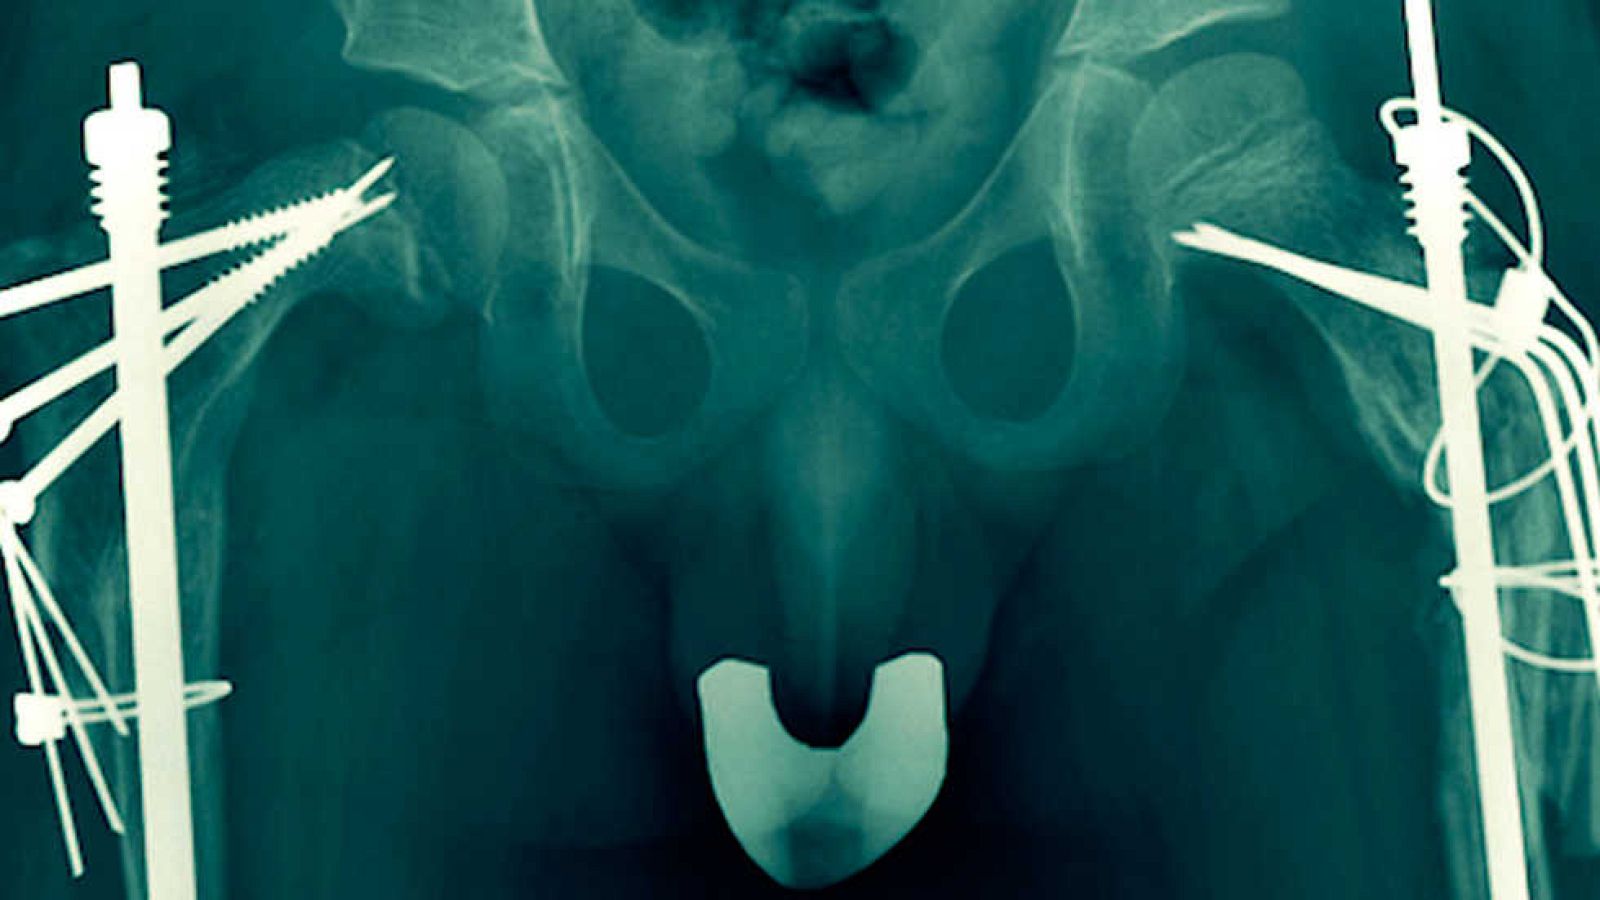

La batalla contra la destrucción del hueso responde a tratamientos farmacológicos y la cirugía, la solución urgente a las múltiples fracturas. Sin embargo, es la genética sobre la que recae la esperanza de los afectados, familiares y profesionales. De ella esperan, que algún día a no mucho tardar, las células óseas del paciente, sean capaces de generar hueso normal. Los especialistas auguran que en cinco o diez años pueden aparecer tratamientos satisfactorios en patologías congénitas.